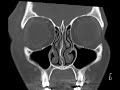

Periorbital Cellulitis

These images show moderate right periorbital soft tissue swelling with thickening of the skin and expansion and infiltration of the subcutaneous fat. There is no evidence of post-septal extension or abscess formation which is commonly the reason for acquiring this study. There is no evidence of sinus disease which can be a cause of the related entity of subperiosteal orbital abscess. Findings are consistent with periorbital cellulitis.